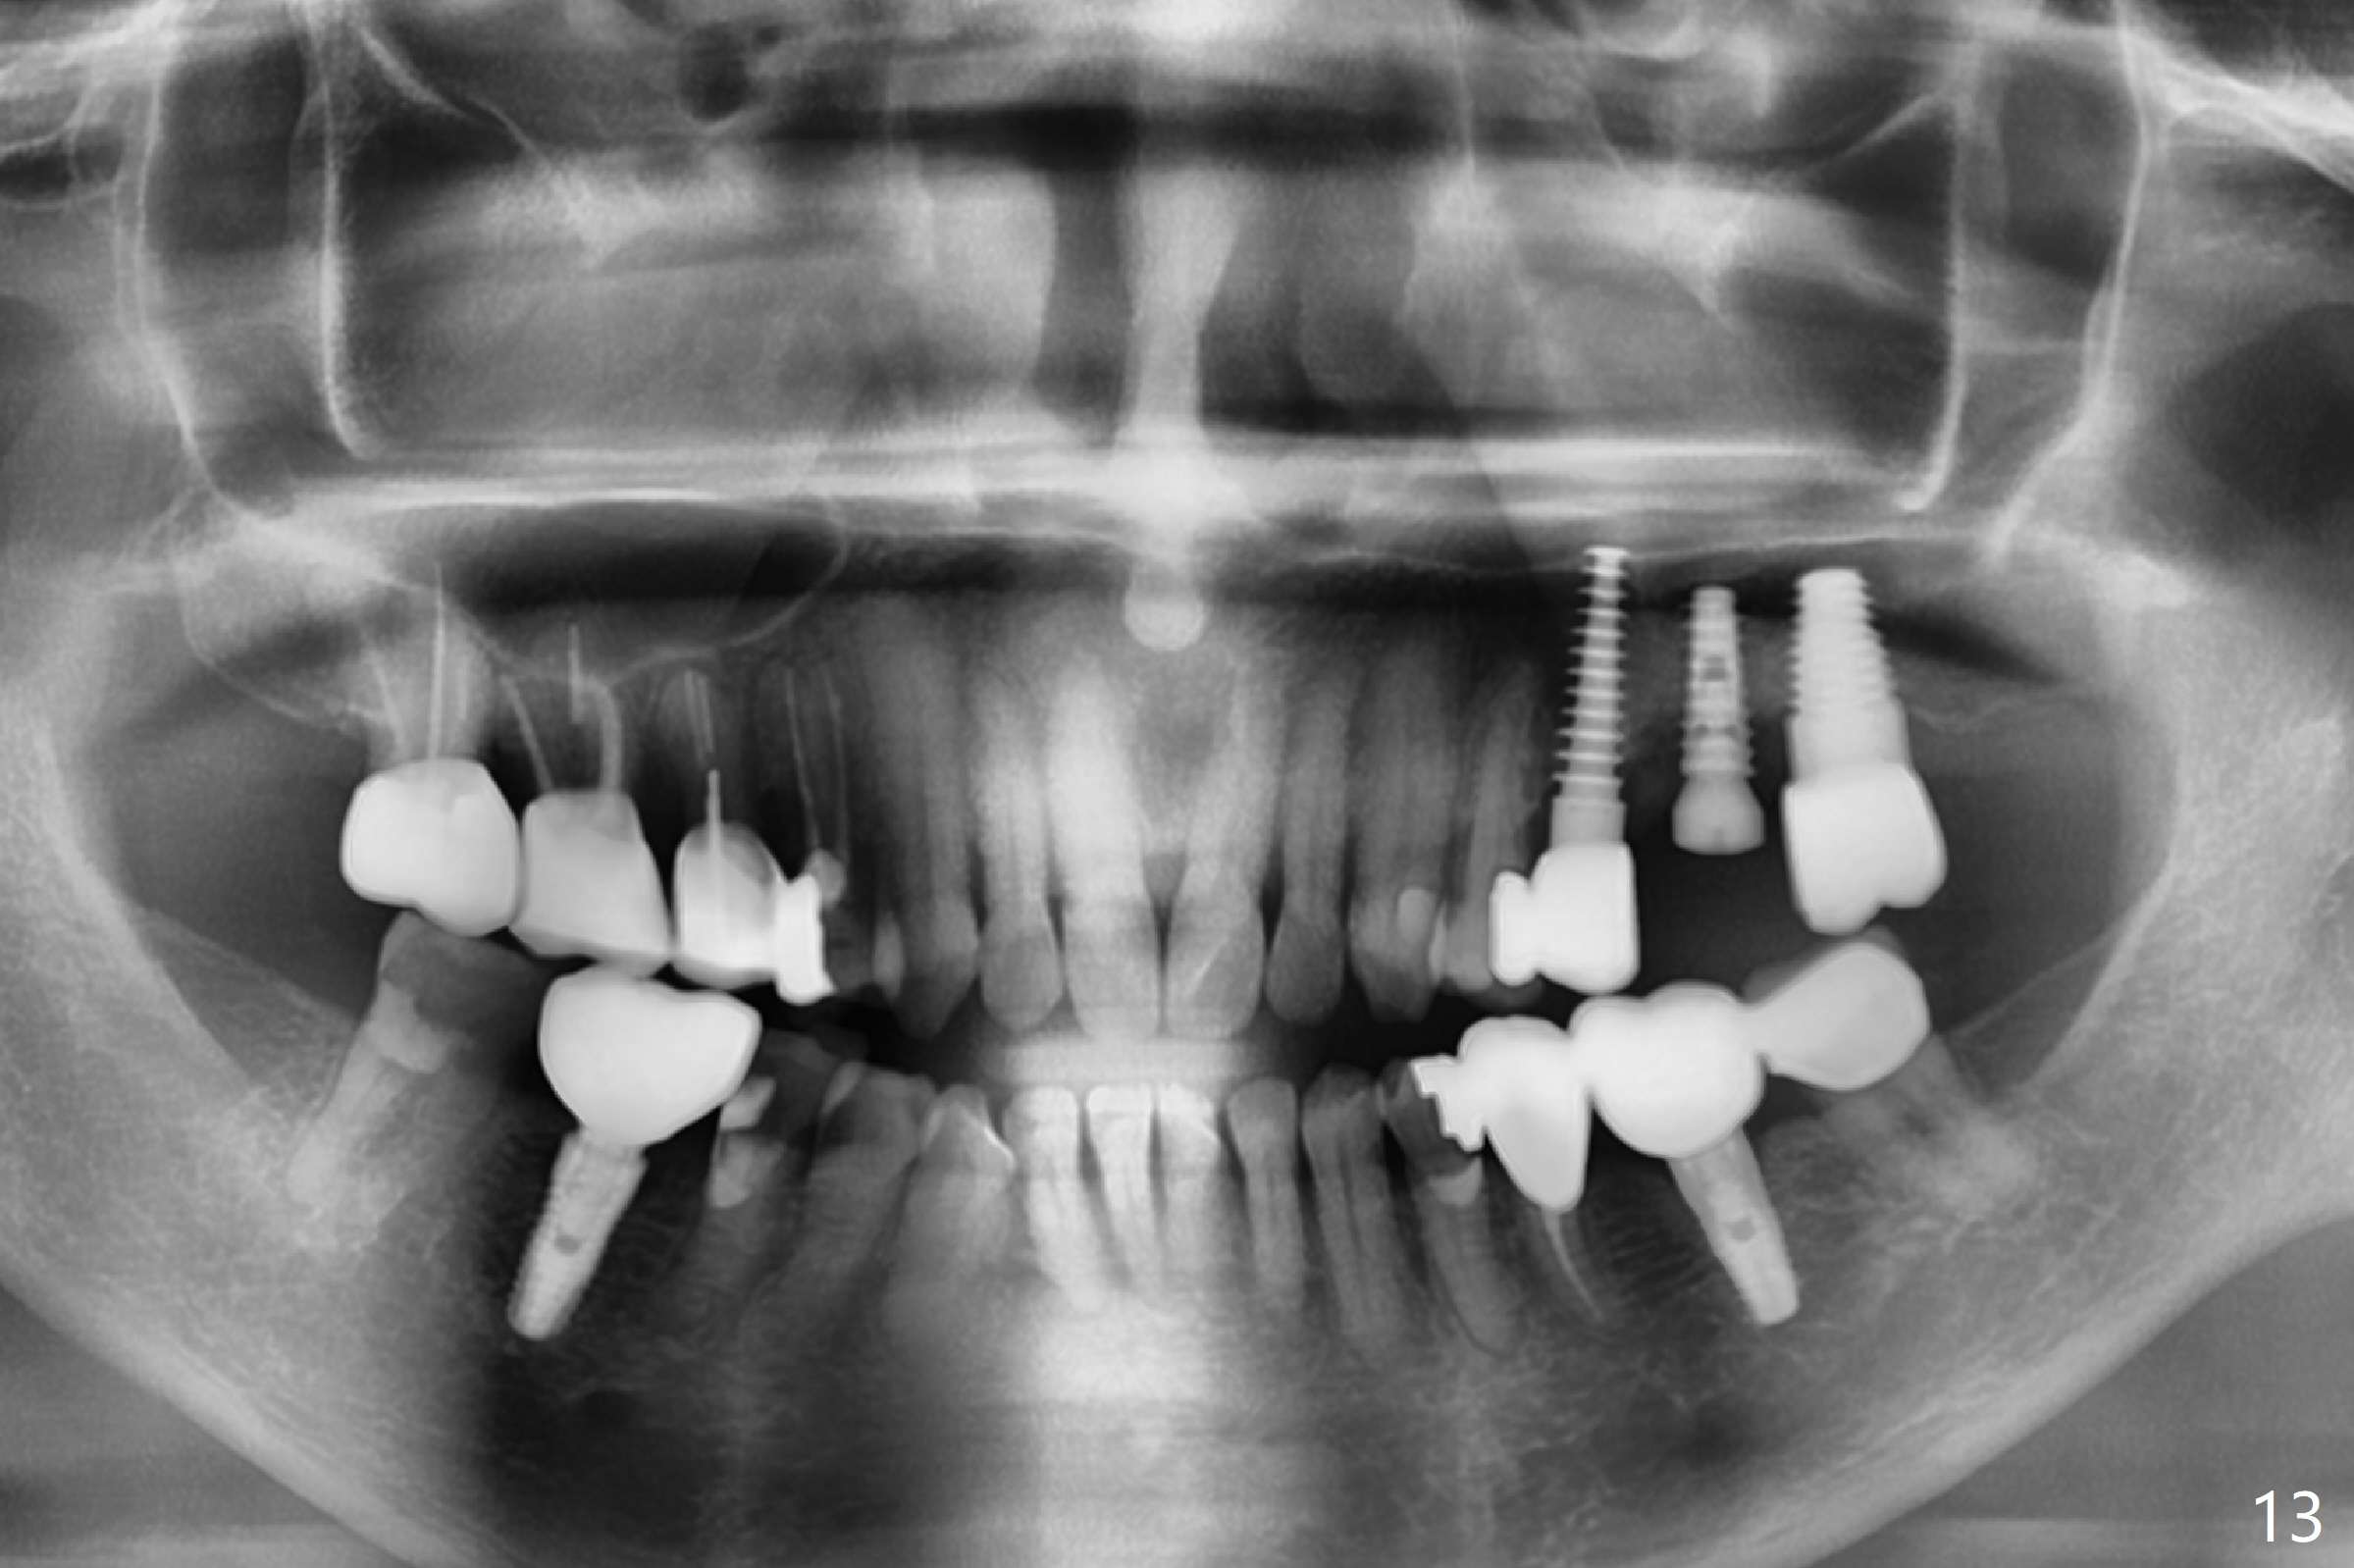

Initial osteotomy in the septum of the tooth #14 is 9 mm, approximately 2 mm from the sinus floor (Fig.1). Subsequent osteotomy depth is 11 mm, followed by insertion of a 4.5x11 mm dummy implant (Fig.2). After use of Magic Drill (MD) 4.8 mm for 9 mm, a 5x11 mm IBS implant is placed with sinus lift without additional bone graft (Fig.3 *). In contrast, autogenous bone (from MD) and Vanilla Graft are meticulously placed in the remaining socket (+) before and after placement of a 6.5x5.7(2) mm abutment. An immediate provisional is fabricated to close the sockets. There is buccal tenderness 1-3 months postop. There is distopalatal implant thread exposure. A healing abutment (5.5x2 mm) is placed. CT confirms thin buccal plate (Fig.4,5). It appears that the implant should have been as palatal as possible. The tenderness remains for the next 2 weeks. When the healing abutment is removed, the implant seems to have been placed shallow, ~ 1 mm subgingival (Fig.6). With local anesthesia, the implant is reversed to clean the coronal threads with Titanium brush and copious irrigation (Fig.7). The implant is then placed ~4 mm subgingival (Fig.8) and slightly subcrestal (Fig.9,10). It appears that the postop bone loss (Fig.9 *, as compared Fig.1,2) makes the implant look to be placed too shallow. When the implant is being placed deeper, the buccal plate feels intact. The early periimplantitis is apparently due to postop bone loss more than buccal placement, although certain degree of buccal bone resorption must occur. A 6x4 mm healing abutment is placed. Left facial swelling develops 2 days post implant elevation (Fig.11,12, as compared to preop (Fig.13)). The left maxillary sinus cloud (Fig.12) appears to be a false positive finding, since the same feature exists prior to implant elevation (Fig.13). Both sinuses look clear prior to implant elevation (Fig.14). Amoxicillin switches to Augmentin and Flagyl, since the patient is reluctant to have the implant removed. Finally the sinus infection is under control. The patient feels left facial swelling 9 months postop (5 months post elevation) and reports left nasal discharge ~ 1 month earlier. There is mild buccal plate tenderness. The implant seems to be buccally placed (Fig.15,16), although there is no significant change radiographically (Fig.17). The implant is removed with bone graft (Fig.18 *). To avoid complication and failure, an immediate implant at the upper 1st molar should be short and placed deep.